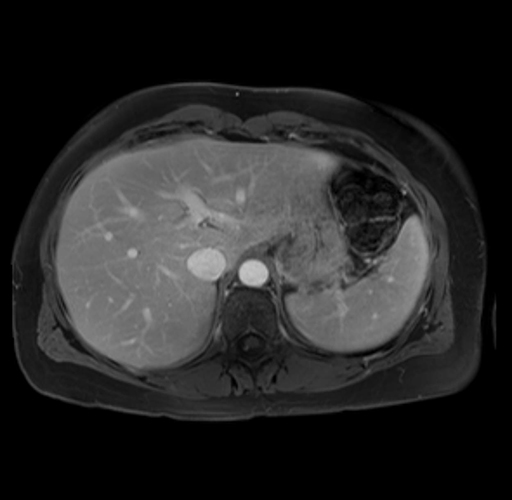

Imaging Analysis

Look through the patient's CT scan to identify any areas of concern for the necessary procedure.

Based on your CT findings, which issue(s) are present and would give reason for "planned slowing down moment(s)" in this case?

Considering a standard distal pancreatectomy procedure, what step(s) of the operation would you do differently in this case?